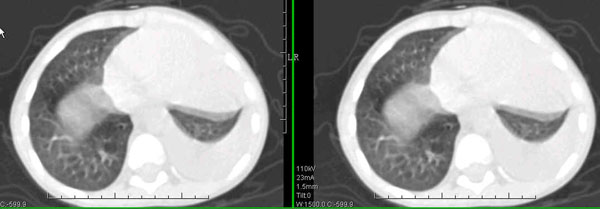

男孩,4岁,发热咳嗽4天。

下面补充ct图片:

此病人是我接手的,发热、咳嗽来做胸透,透视见左侧肺野大部密实,纵隔、心影明显左移,呼吸示纵隔摆动、膈肌矛盾运动(透视下采集了几幅图片),左肺动度明显减弱。询问病人家长,没有吃花生米等呛咳史。由于其影像特征明显,当时诊断:考虑左侧支气管异物并阻塞性肺不张、肺炎。

病人去上级医院支气管镜取出了异物。今天询问上级医院耳鼻喉科主任(是我同学),得知病人异物为胶冻样合并有少许白色粉末,后小儿说晚上喝药片时呛咳过,考虑当时为药片阻塞;另外支气管镜检发现小儿左侧支气管发育略窄,经住院抗炎治疗,现病人基本康复。

多谢各位关注及精彩点评!追踪病人结果时才知道还做过ct检查!对不起!有点晚了,刚刚下载,上传供大家参考!